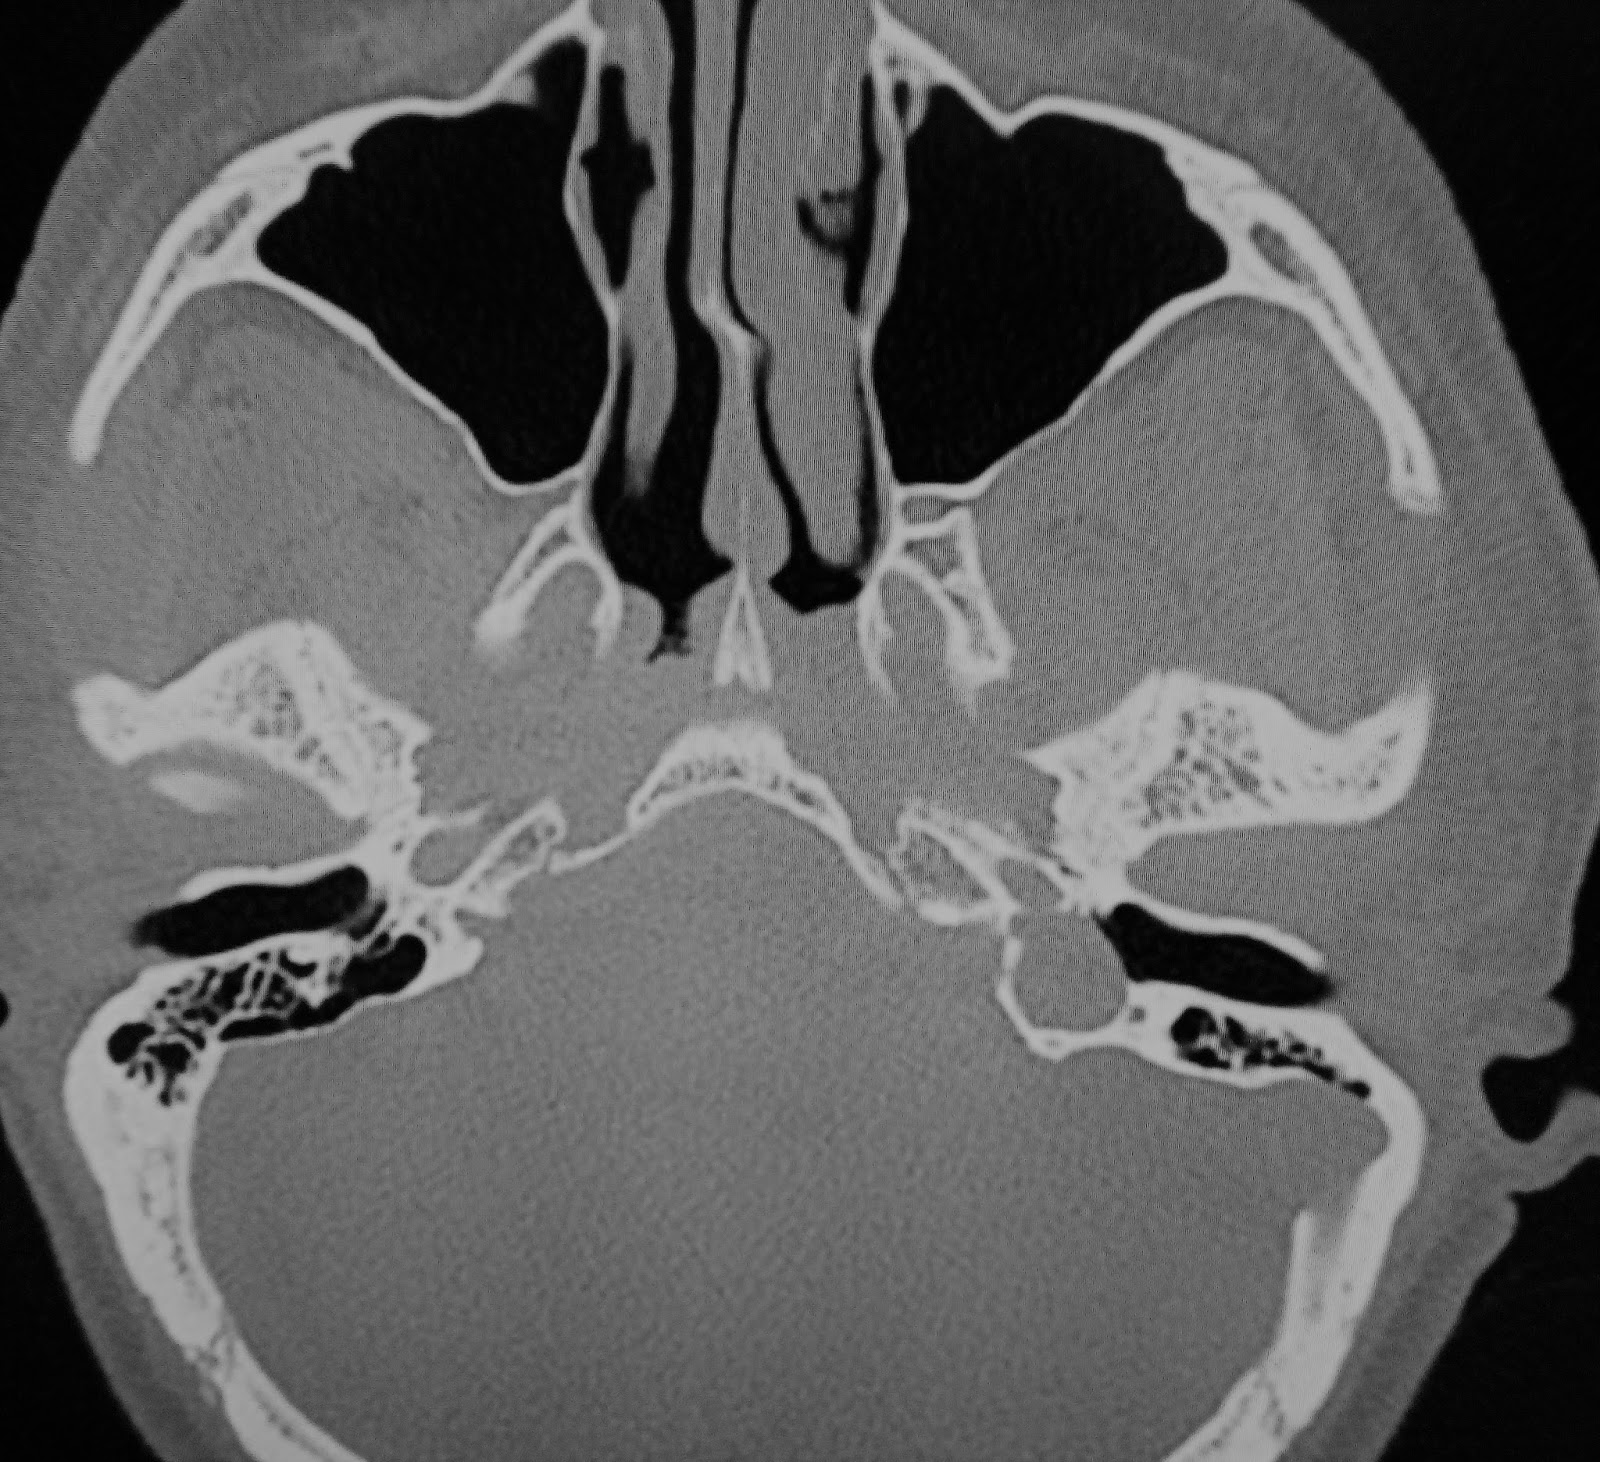

High resolution CT scan of the temporal bone in axial plane obtained Jugular Bulbs Definition   the gross and microscopic anatomy of the jugular bulb is discussed, and selected illustrations of temporal bone sections.  the jugular bulb is the connection between the sigmoid sinus and the internal jugular vein.    — a high riding jugular bulb indicates the dome (roof) of the jugular bulb extends more superiorly in the petrous temporal bone than is.. Jugular Bulbs Definition.